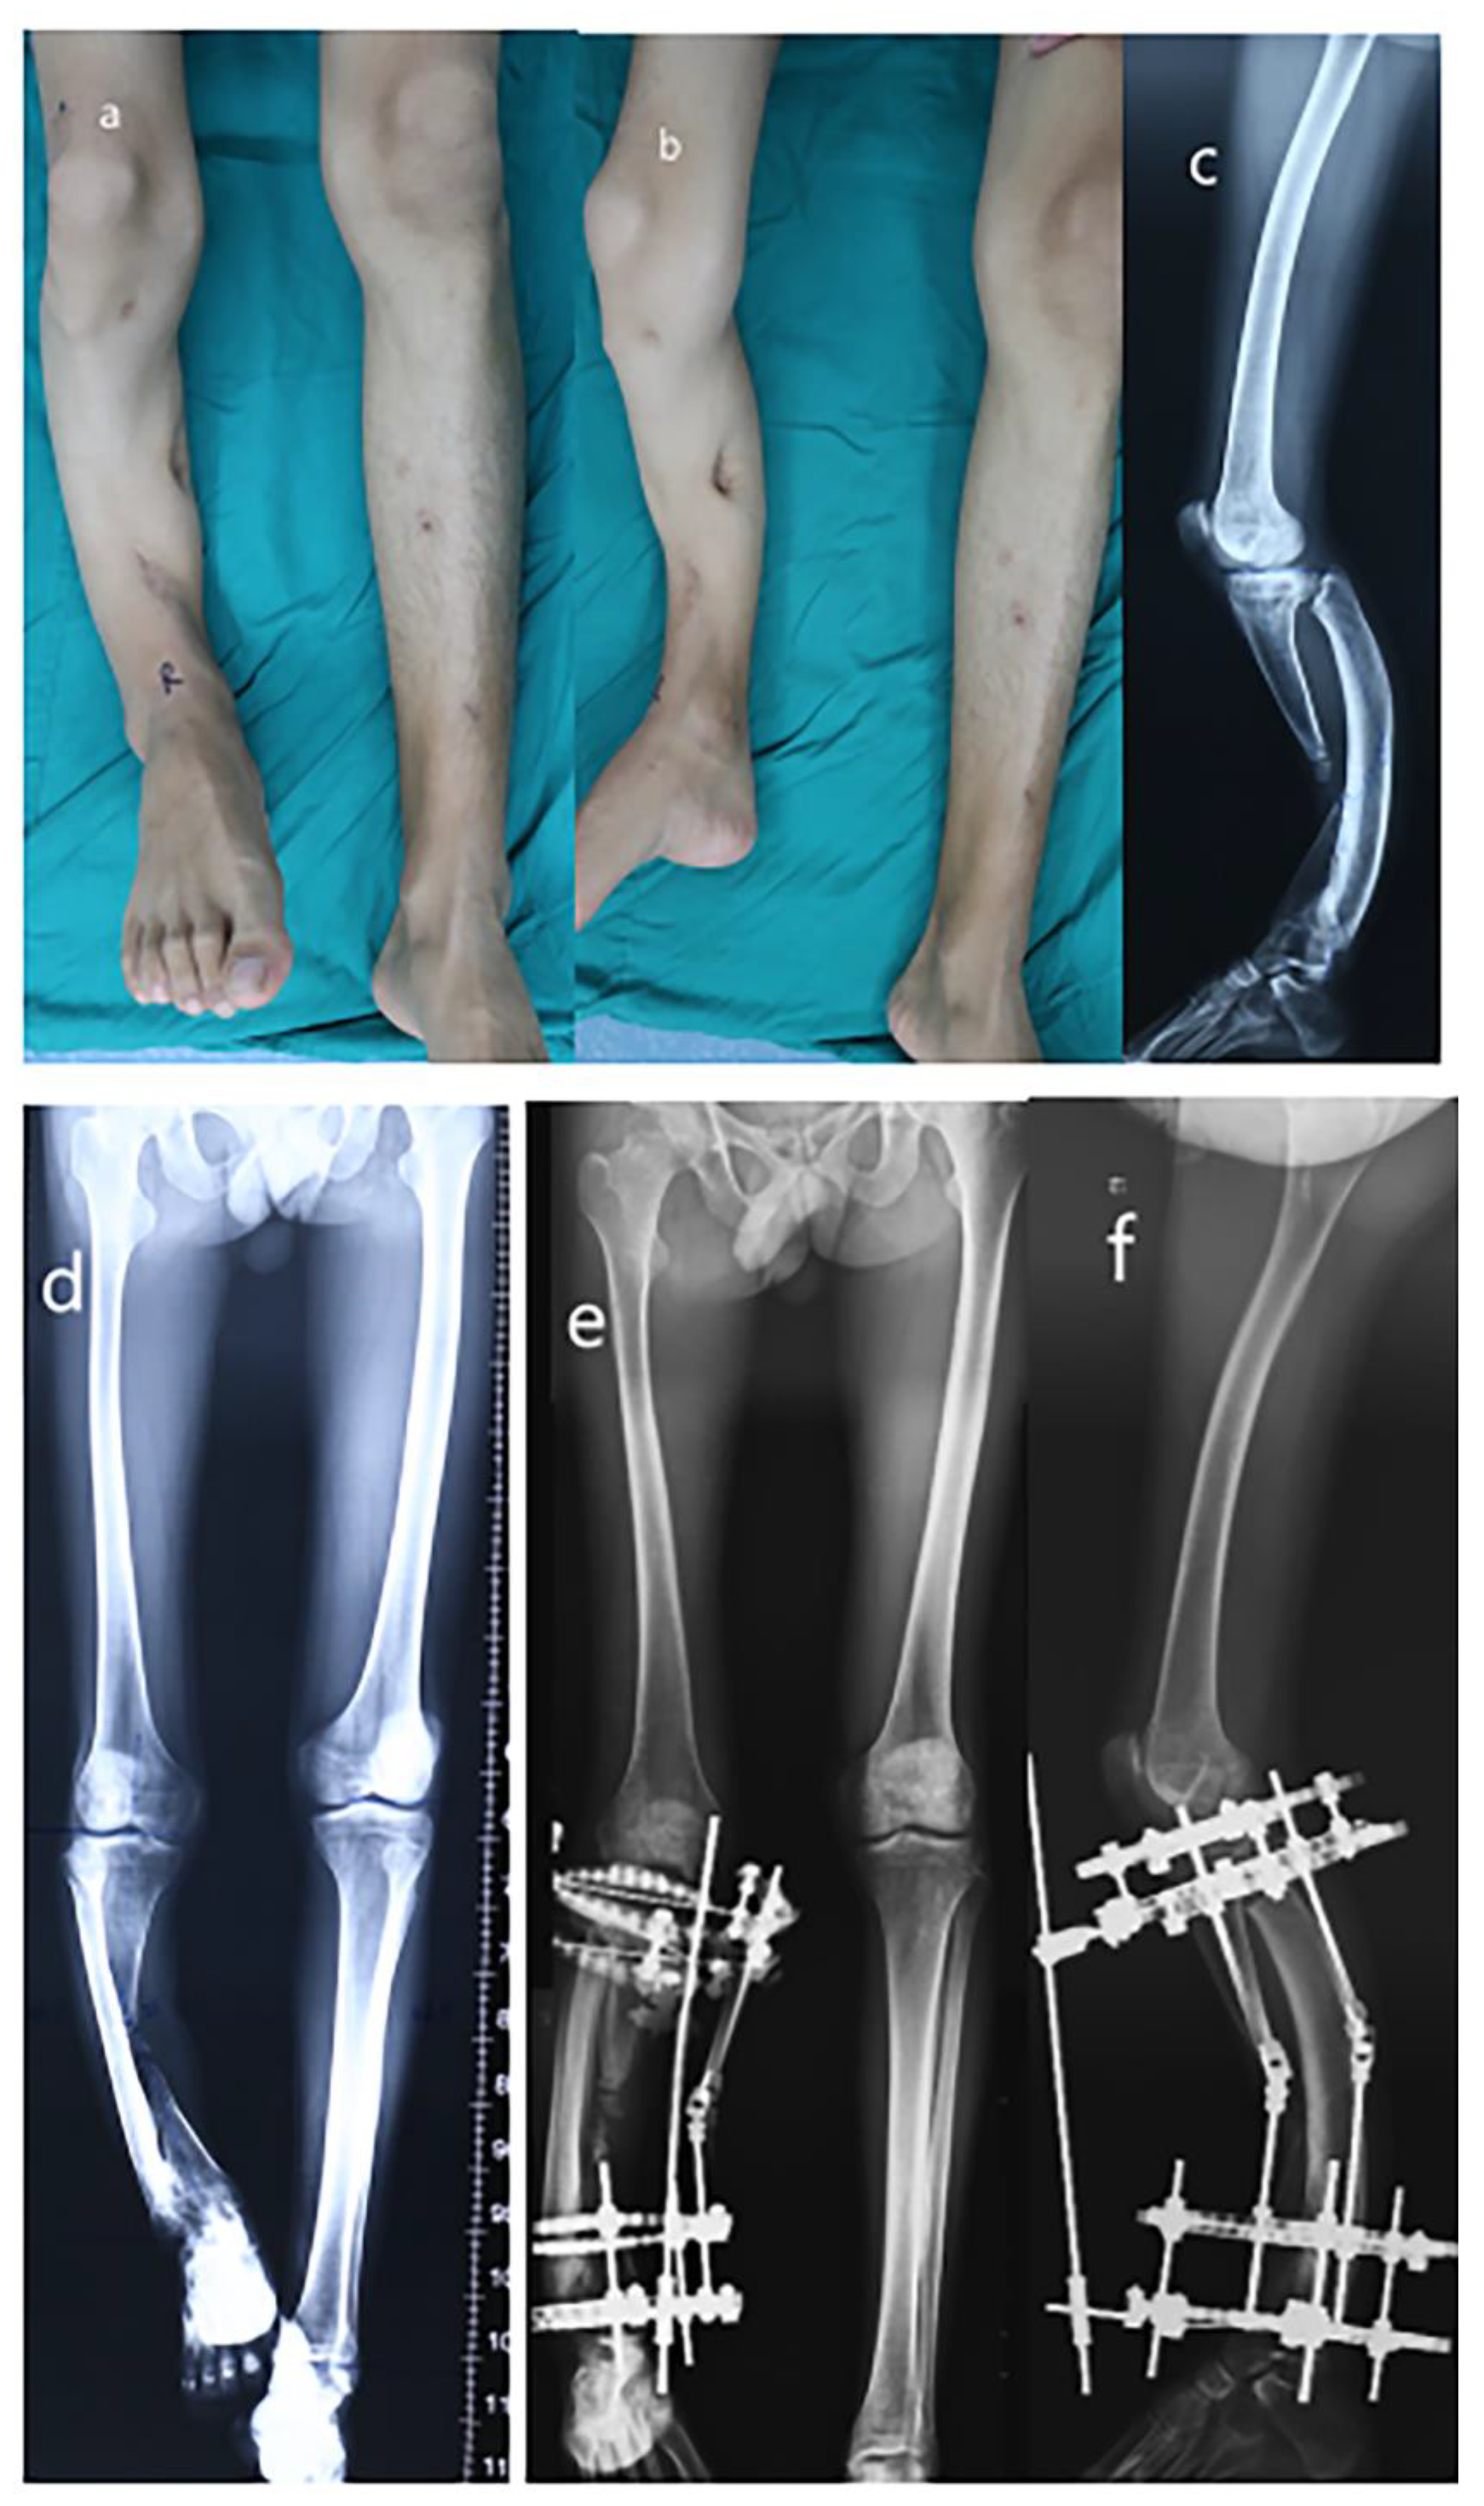

Figure 1.

Radiograph of a 24-year-old male of severe limb length discrepancy and tibia varus. (a) Appearance (AP view); (b) Appearance (lateral view); (c) Preoperative later view radiograph; (d) Preoperative AP view radiograph; (e) Postoperative AP view radiograph; (f) Postoperative lateral view radiograph.